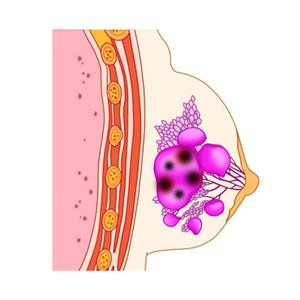

유방암은 여성에게 가장 흔한 암 중 하나로, 조기 발견과 치료가 생존율에 큰 영향을 미칩니다. 이번 포스팅에서는 유방암 초기증상, 2기 생존율, 수술 후 회복기간에 대해 자세히 알아보겠습니다.

유방암 초기에는 증상이 명확하지 않을 수 있지만, 아래와 같은 변화를 주의 깊게 살펴보는 것이 중요합니다.

- 유방에 덩어리(종괴) 발생

유방이나 겨드랑이 부근에서 통증이 없는 단단한 혹이 만져질 수 있습니다. - 유방 모양 변화

한쪽 유방이 비대칭적으로 변하거나 크기와 모양이 변합니다. - 피부 변화

유방 피부가 오렌지 껍질처럼 두꺼워지거나 함몰됩니다. - 유두 이상

유두에서 분비물이 나오거나, 유두가 함몰되는 증상이 나타날 수 있습니다. - 통증

초기에는 드물지만, 유방이나 겨드랑이에 지속적인 통증이 동반될 수 있습니다.